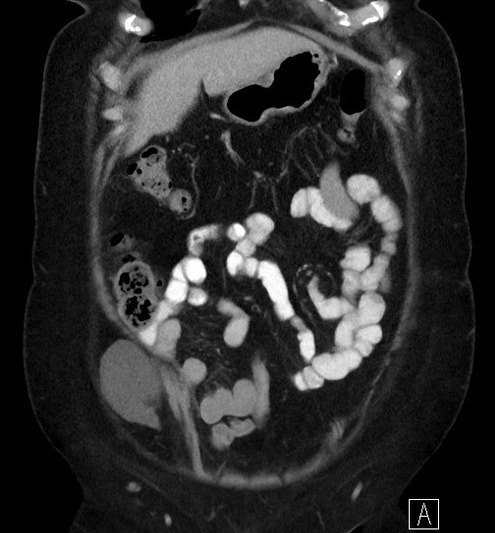

Thoát vị thành bụng

Thoát vị thành bụng - Ảnh 4

» Thông tin: Nữ giới – 50 tuổi.

» Lâm sàng: Đau hố chậu phải.